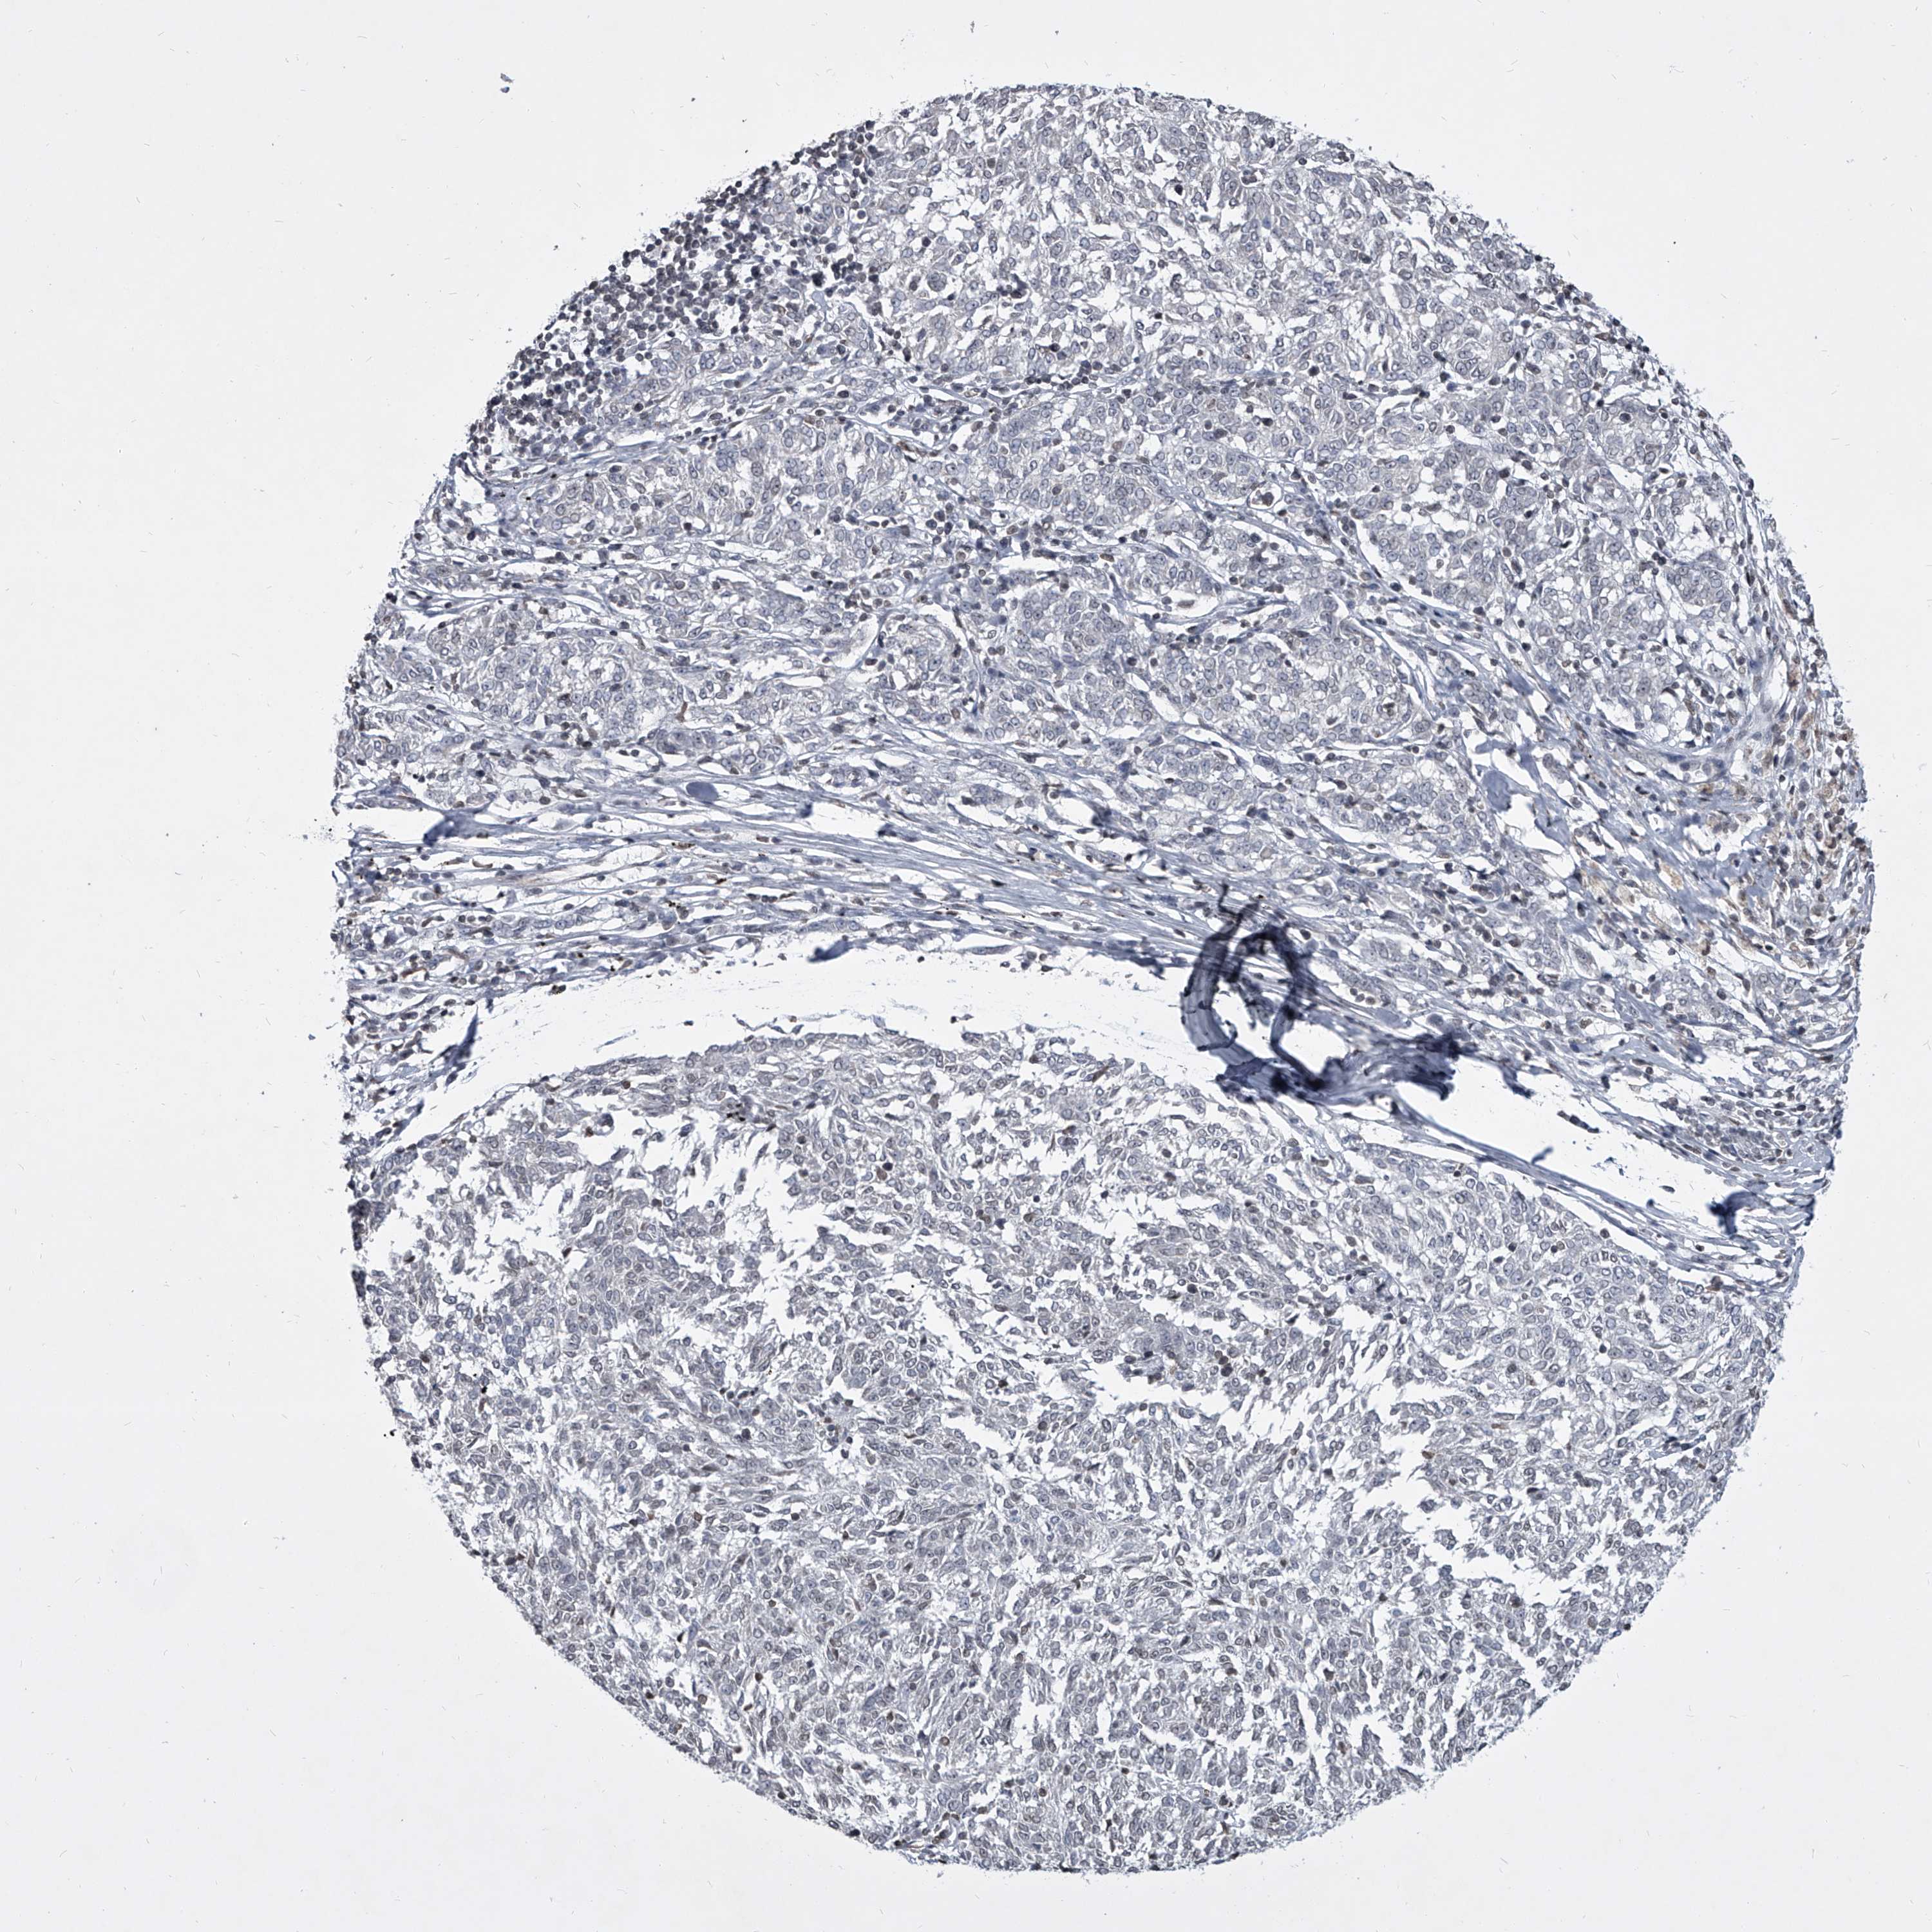

MELANOMA - Protein expressioni

A mouse-over function shows sample information and annotation data. Click on an image to view it in a full screen mode. Samples can be filtered based on level of antibody staining by selecting one or several of the following categories: high, medium, low and not detected. The assay and annotation is described here.

Note that samples used for immunohistochemistry by the Human Protein Atlas do not correspond to samples in the TCGA dataset.

Antibody stainingi

Antibody staining in the annotated cell types in the current human tissue is reported as not detected, low, medium, or high, based on conventional immunohistochemistry profiling in selected tissues. This score is based on the combination of the staining intensity and fraction of stained cells.

Each image is clickable and will lead to virtual microscopy that enables deeper exploration of all samples and also displays staining intensity scores, fraction scores and subcellular localization as well as patient and tissue information for each sample.

Antibody HPA031600

Staining

High

Medium

Low

Not detected

Intensity

Strong

Moderate

Weak

Negative

Quantity

>75%

75%-25%

<25%

None

Location

Nuclear

Cytoplasmic/membranous

Cytoplasmic/membranous,nuclear

Malignant melanoma, NOS

Malignant melanoma, Metastatic site